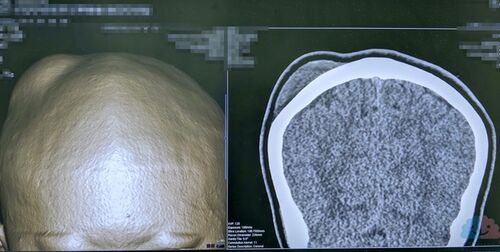

いつまでも治らずにブヨブヨしているたんこぶの処置。

先日、「たんこぶが治らずにブヨブヨしているので診て欲しい」というご相談を受けた。 聞くと、2週間前に転んで頭を打撲し、その後じわじわとたんこぶが膨らんでき改善しないため受診したという経緯だった。